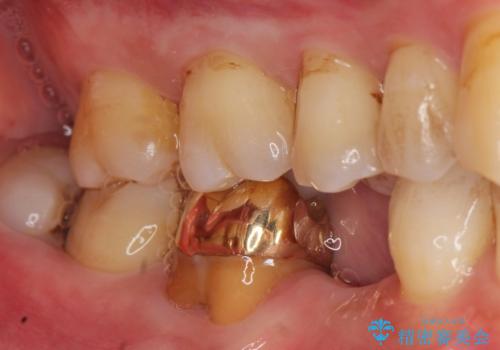

![[ 歯牙破折 ] 違和感のある大臼歯 ブリッジ治療の症例 治療前](https://seimitsushinbi.jp/wp/wp-content/uploads/2021/08/IMG_9577-500x350.jpg?v=1629711075)